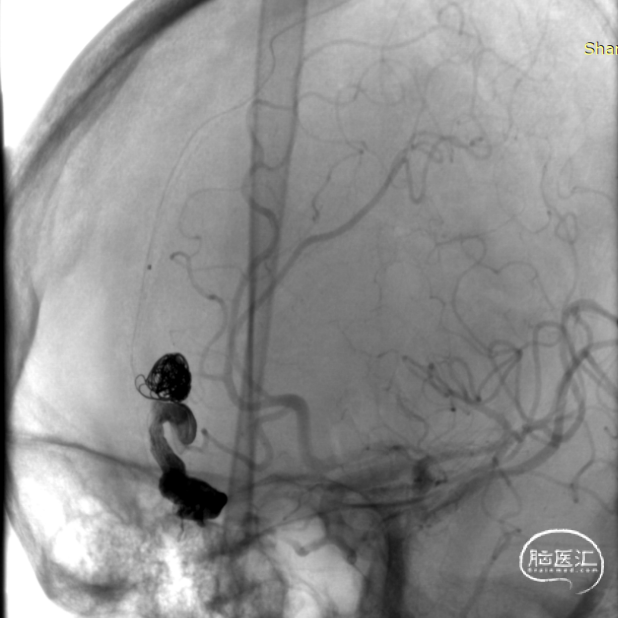

顺利“安全”地注入Onyx18,瘘口完全栓塞,造影提示一期治愈,正常皮层引流静脉得以保留。

术后即刻造影见DAVF完全栓塞。